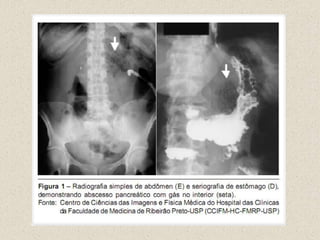

Exames de imagemRX SIMPLESTCUSGCPRERM

RAIO XAlça sentinelaDerrame pleural à esquerdaAumento do arco duodenalSEM INDICAÇÃO NA ESTRATIFICAÇÃO DA GRAVIDADE

RAIO X